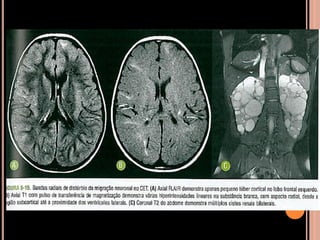

 ENCÉFALO

Túberes corticais;

Nódulos subependimários;

Astrocitoma subependimário de células

gigantes(ASCG);

Lesões de substância branca por distúrbios de

migração neuronal;

Achados de imagem

Achados de imagem – Ressonância magnética

 Recomendações

RM: método de escolha;

anual em paciente com CET e nódulos

subependimários adjacentes ao forame de Monro,

parcialmente calcificados e com impregnação pelo

Gd (crescimento e obstrução)  favorece ASCG e

indica cirurgia precoce;

TC sem contraste: só para ver nódulos

subependimários calcificados;